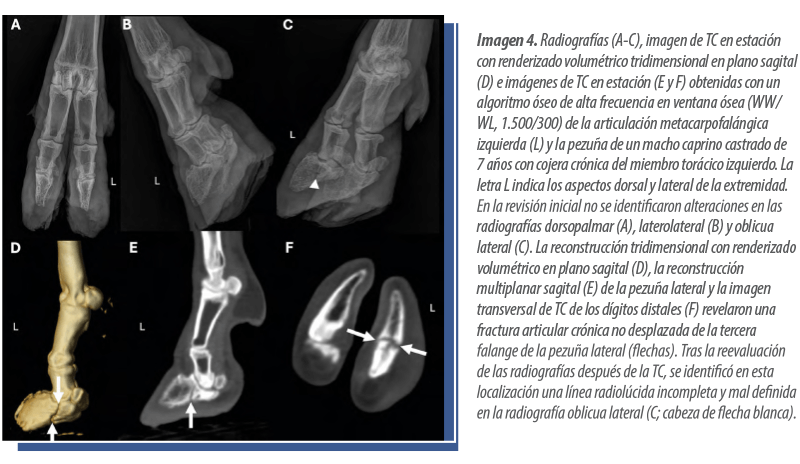

En los tres casos de TC de extremidades distales, se identificaron lesiones como artritis séptica asociada a osteomielitis de la articulación metacarpofalángica y del metacarpo distal (Imagen 3), así como una fractura no desplazada de la tercera falange en una pezuña anterior (Imagen 4).

La cojera fue la indicación más frecuente para la realización de TC en estación de las extremidades distales y los diagnósticos por imagen obtenidos en estos casos estuvieron relacionados principalmente con patología ósea.

En el ganado bovino, la cojera se localiza con mayor frecuencia en regiones distales al menudillo. Por ello, la TC en estación de las extremidades distales puede resultar útil en casos de cojera de difícil diagnóstico o en situaciones de inicio temprano de la patología que no se identifican mediante radiografía o ecografía, contribuyendo así a orientar el tratamiento.

Una de las ventajas de la TC en estación de las extremidades distales frente a la TC en decúbito es que permite realizar la exploración en una posición natural de carga de peso, lo que facilita la evaluación de posibles asimetrías entre extremidades y la identificación de alteraciones mediante la comparación con la extremidad contralateral.